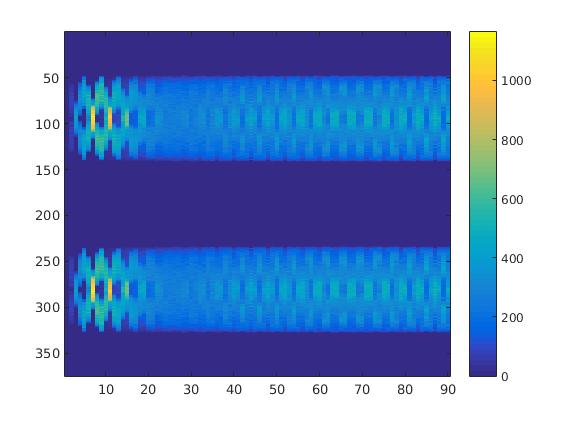

To simulate the synthesized SPECT data, we apply a Radon transform assuming a double detector gamma camera, which counts photons from two opposing projection angles per time step. For the more simple data set, we let the camera rotate clockwise around two degree per time step, in case of the complex data set we used modified projection angles, i.e. the camera alternatingly projects from an angle of i and 45+i degrees, in order to simplify the reconstruction. Each collimator consists of detector bins, so we obtain data points per time step and projection angle. The resulting sinogram data of the two underlying data sets are shown in figure 3.

In a first test, every image sequence was reconstructed out of the exact given sinograms. Additionally we tested noise corrupted data by first scaling the sinogram by a parameter , corrupting them with Poisson noise via the MATLAB imaging toolbox command imnoise and finally rescaling the image to the original range (see figure 4). The average count number per time step (i.e. the average of the discrete -norm of the data at each time step) is approximately in case of the heart-shaped data set and ca. in case of the rat liver simulation. The results at a certain number of time steps can be seen in figure 6 and 7. For comparison, we additionally performed a reconstruction with a simple alternating EM method, keeping the assumption that the tracer can be modelled as a sum of indicator functions and subconcentration curves, but neglecting any regularization terms. In all tests, the outer iteration number was set to 1000 with 10000 inner iterations per subproblem, to obtain a result within a reasonable time period. As stopping criterion, we chose the primal dual residual (cp. [12]) for the inner and the maximum over the Frobenius norms of and for the outer iterations. The results are displayed in 6 and 7 respectively.

In two different tests we fixed the number of events counted by the detector equal to (resp. ) times the average concentration in one pixel. The resulting sinogram images of the accumulated counts in each bin are shown in figure 9.